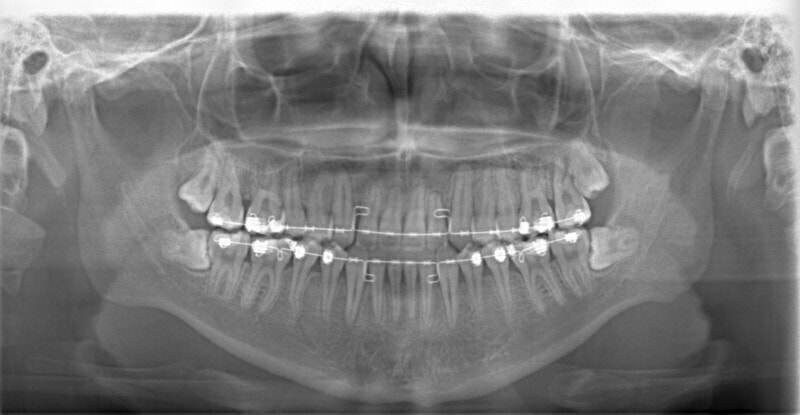

治療中のレントゲンです。

7番、8番の状態や歯根のパラレリング(平行性)をチェックしています。

左上2番の歯根の状態もなんとかもちそうです。